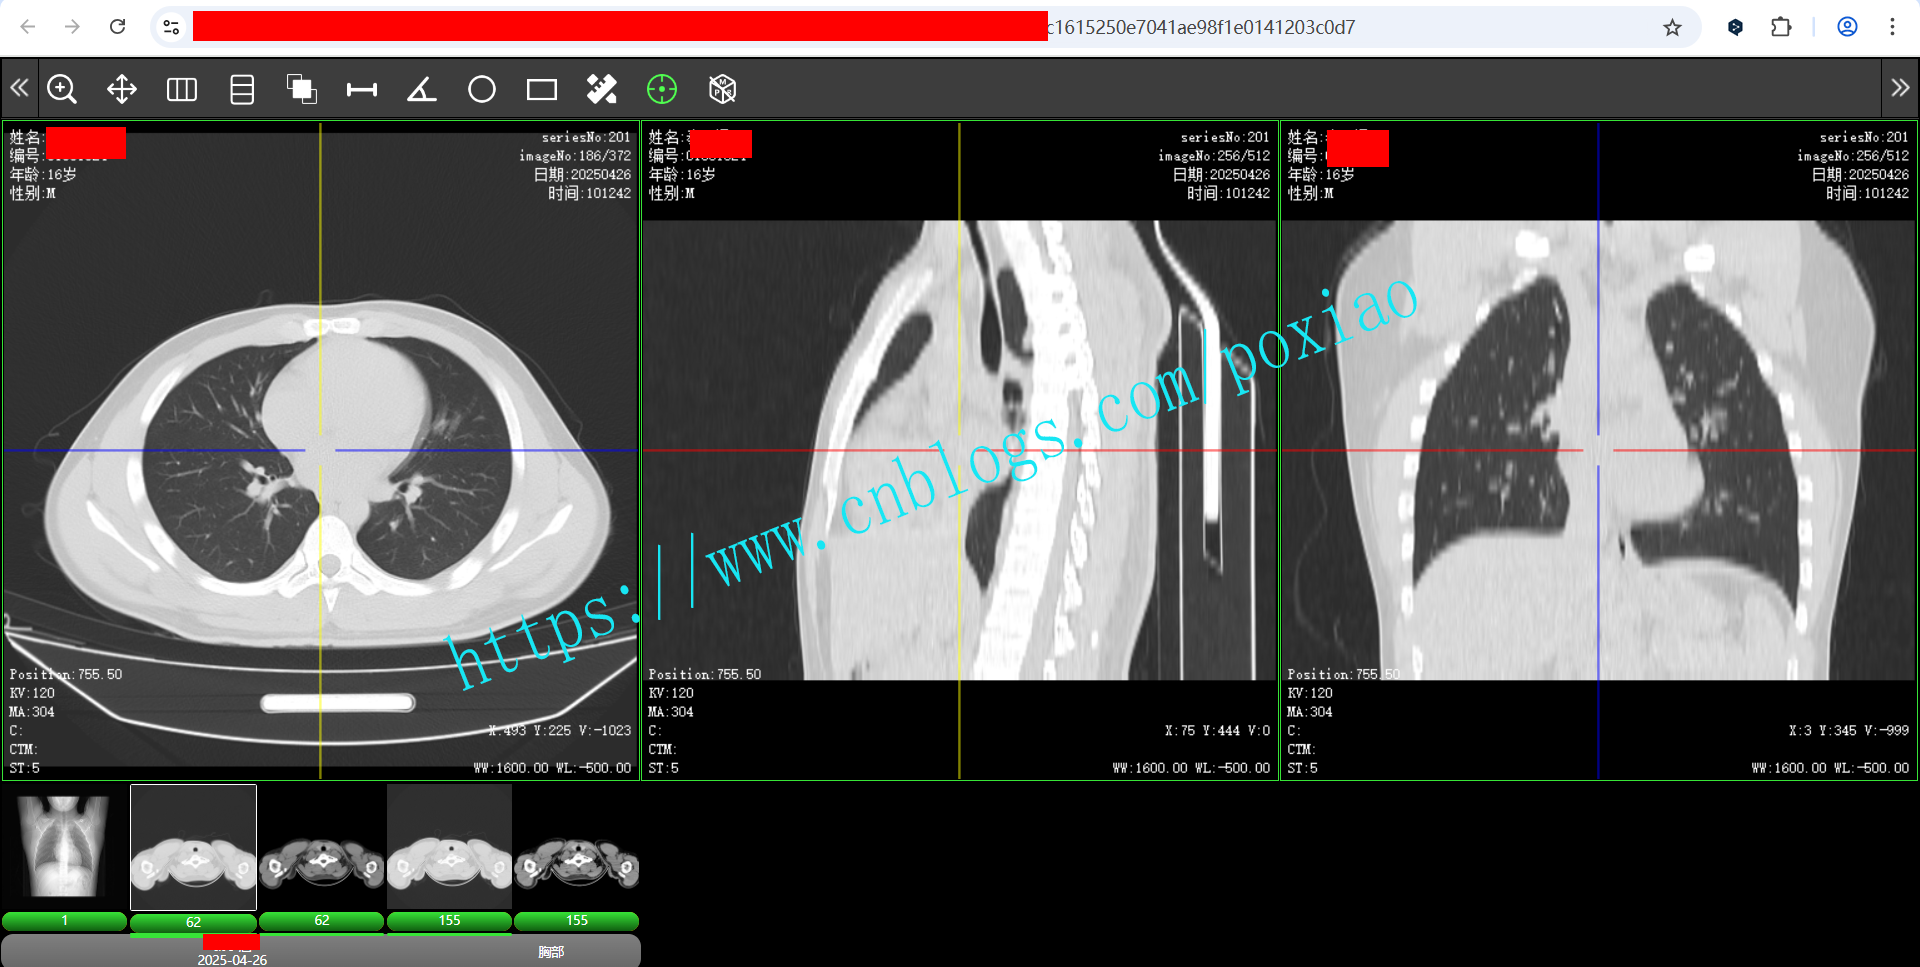

2.支持3D定位功能,点击序列上的可疑病灶点,其它序列可以定位到同一层,并定位到相同的病灶点上。

3.支持MPR浏览功能